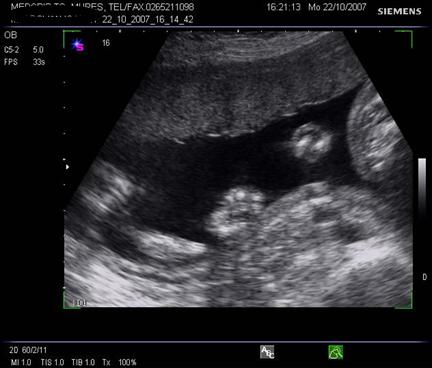

Fig. nr.205. Placenta fundica si posterioara ( normal inserata, cu sageata ) la o sarcina de 16 sapt.